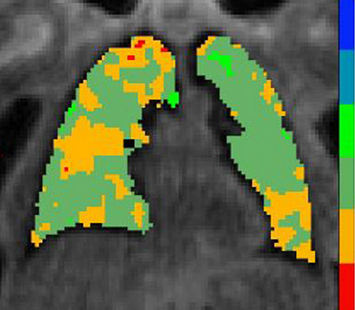

Lower rates of gas exchange in the lungs may contribute to impaired cognitive function ("brain fog") tied to long COVID, according to a small study to be presented at next week's Radiological Society of North America's (RSNA's) annual meeting in Chicago.

University of Iowa researchers in Iowa City evaluated the link between pulmonary gas exchange on magnetic resonance imaging (MRI), structural and functional brain MRI, lung-function tests, and performance on cognitive tests in long-COVID patients.

The findings suggest that impaired pulmonary gas exchange may be related to cognitive dysfunction and diminished brain gray-matter and white-matter volumes in long-COVID patients. They also indicate that increased cerebral blood flow may be tied to decreased gas exchange in these patients, the authors said.